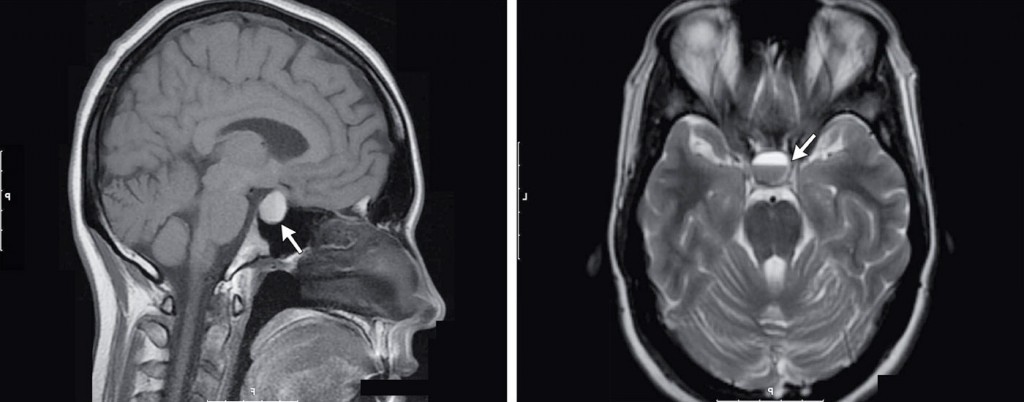

Гипоталамус — высший регулятор нейроэндокринный системы, расположенный в базальном отделе головного мозга. Он участвует в регуляции вегетативных функций организма, отвечающих за артериальное давление, проницаемость сосудов, теплорегуляцию и теплоотдачу, аппетит, обменные процессы, регуляцию сна и психической деятельности. Гипоталамус осуществляет регуляцию деятельности периферических желёз внутренней секреции через гипофиз.